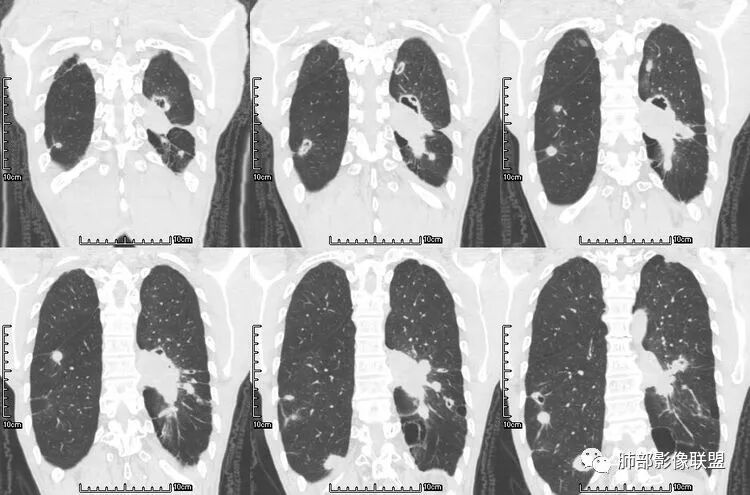

老年男性,咳嗽,咳痰带血2月,左下肺可见一团块影,深分叶,胸膜牵拉,可见坏死,坏死边界清,考虑恶性,双肺多发散在结节影,可见分叶,空洞,胸膜牵拉,考虑转移瘤;

患者老年男性,咳嗽、咳痰、痰中带血伴胸闷2月余。长期大量吸烟史。查肝肾功能、血糖、血脂、心肌酶、电解质、血沉、C反应蛋白、抗“O”、类风湿因子、抗核抗体谱无明显异常。肿瘤标志物提示NSE、CYFRA21-1稍升高。胸部CT:肺气肿背景,左肺下叶后基底段不规则肿块影,见支气管截断,内见大片状低密度区及部分血管影,增强轻度强化,远端空洞形成。双肺多发不规则实性结节影、见毛刺、胸膜牵拉及血管集束,结节内见空洞形成,部分可见血管影,多位于胸膜下。双肺见多发肺大泡。综合考虑左下肺恶性病变并双肺转移。鳞癌或淋巴瘤可能。鉴别血管炎性病变及真菌感染。

张延军:双肺多发结节,空洞影,后者洞壁厚薄不均匀,部分腔内丝丝落落,呈分叶征,边缘见毛刺影,病灶大部分位于胸膜下,与血管相连,右肺下叶前基底段结节近段支气管截断,远端见空腔。左肺下叶病灶密度不均,背段支气管壁增厚,管腔狭窄。考虑1.双肺下叶占位性病变伴肺内空洞性转移 2.多原发的占位 3.肉芽肿性血管炎代排。

本病例左肺下叶肿块,有深分叶、毛刺、胸膜牵拉凹陷、支气管截断及纵隔内淋巴结肿大等征象,都均支持病灶为恶性,如腺癌,而且叶间裂的多发结节也提示是腺癌来源可能大;双肺多发结节、肿块,大部分病灶有分叶、毛刺及胸膜凹陷的恶性征象,与原发肿瘤本身的性质有关,所以应该与左肺下叶肿块同源,而且双肺多发病灶内空洞也具有多样性;

此病例中空洞形态多样,内壁不光整,有分隔影,周围未见明显卫星灶及钙化灶,结核不太符合;患者病史慢性病史,无明显发热,缺乏中毒临床表现,急性感染基本排除;各种中性粒细胞胞浆抗体阴性,没有鼻窦炎,肾脏等病史,基本排除血管炎;霉菌性空洞常见于免疫机能低下者, 常为空洞、肺炎、伴“ 晕圈”征的结节及支气管扩张合并存在。